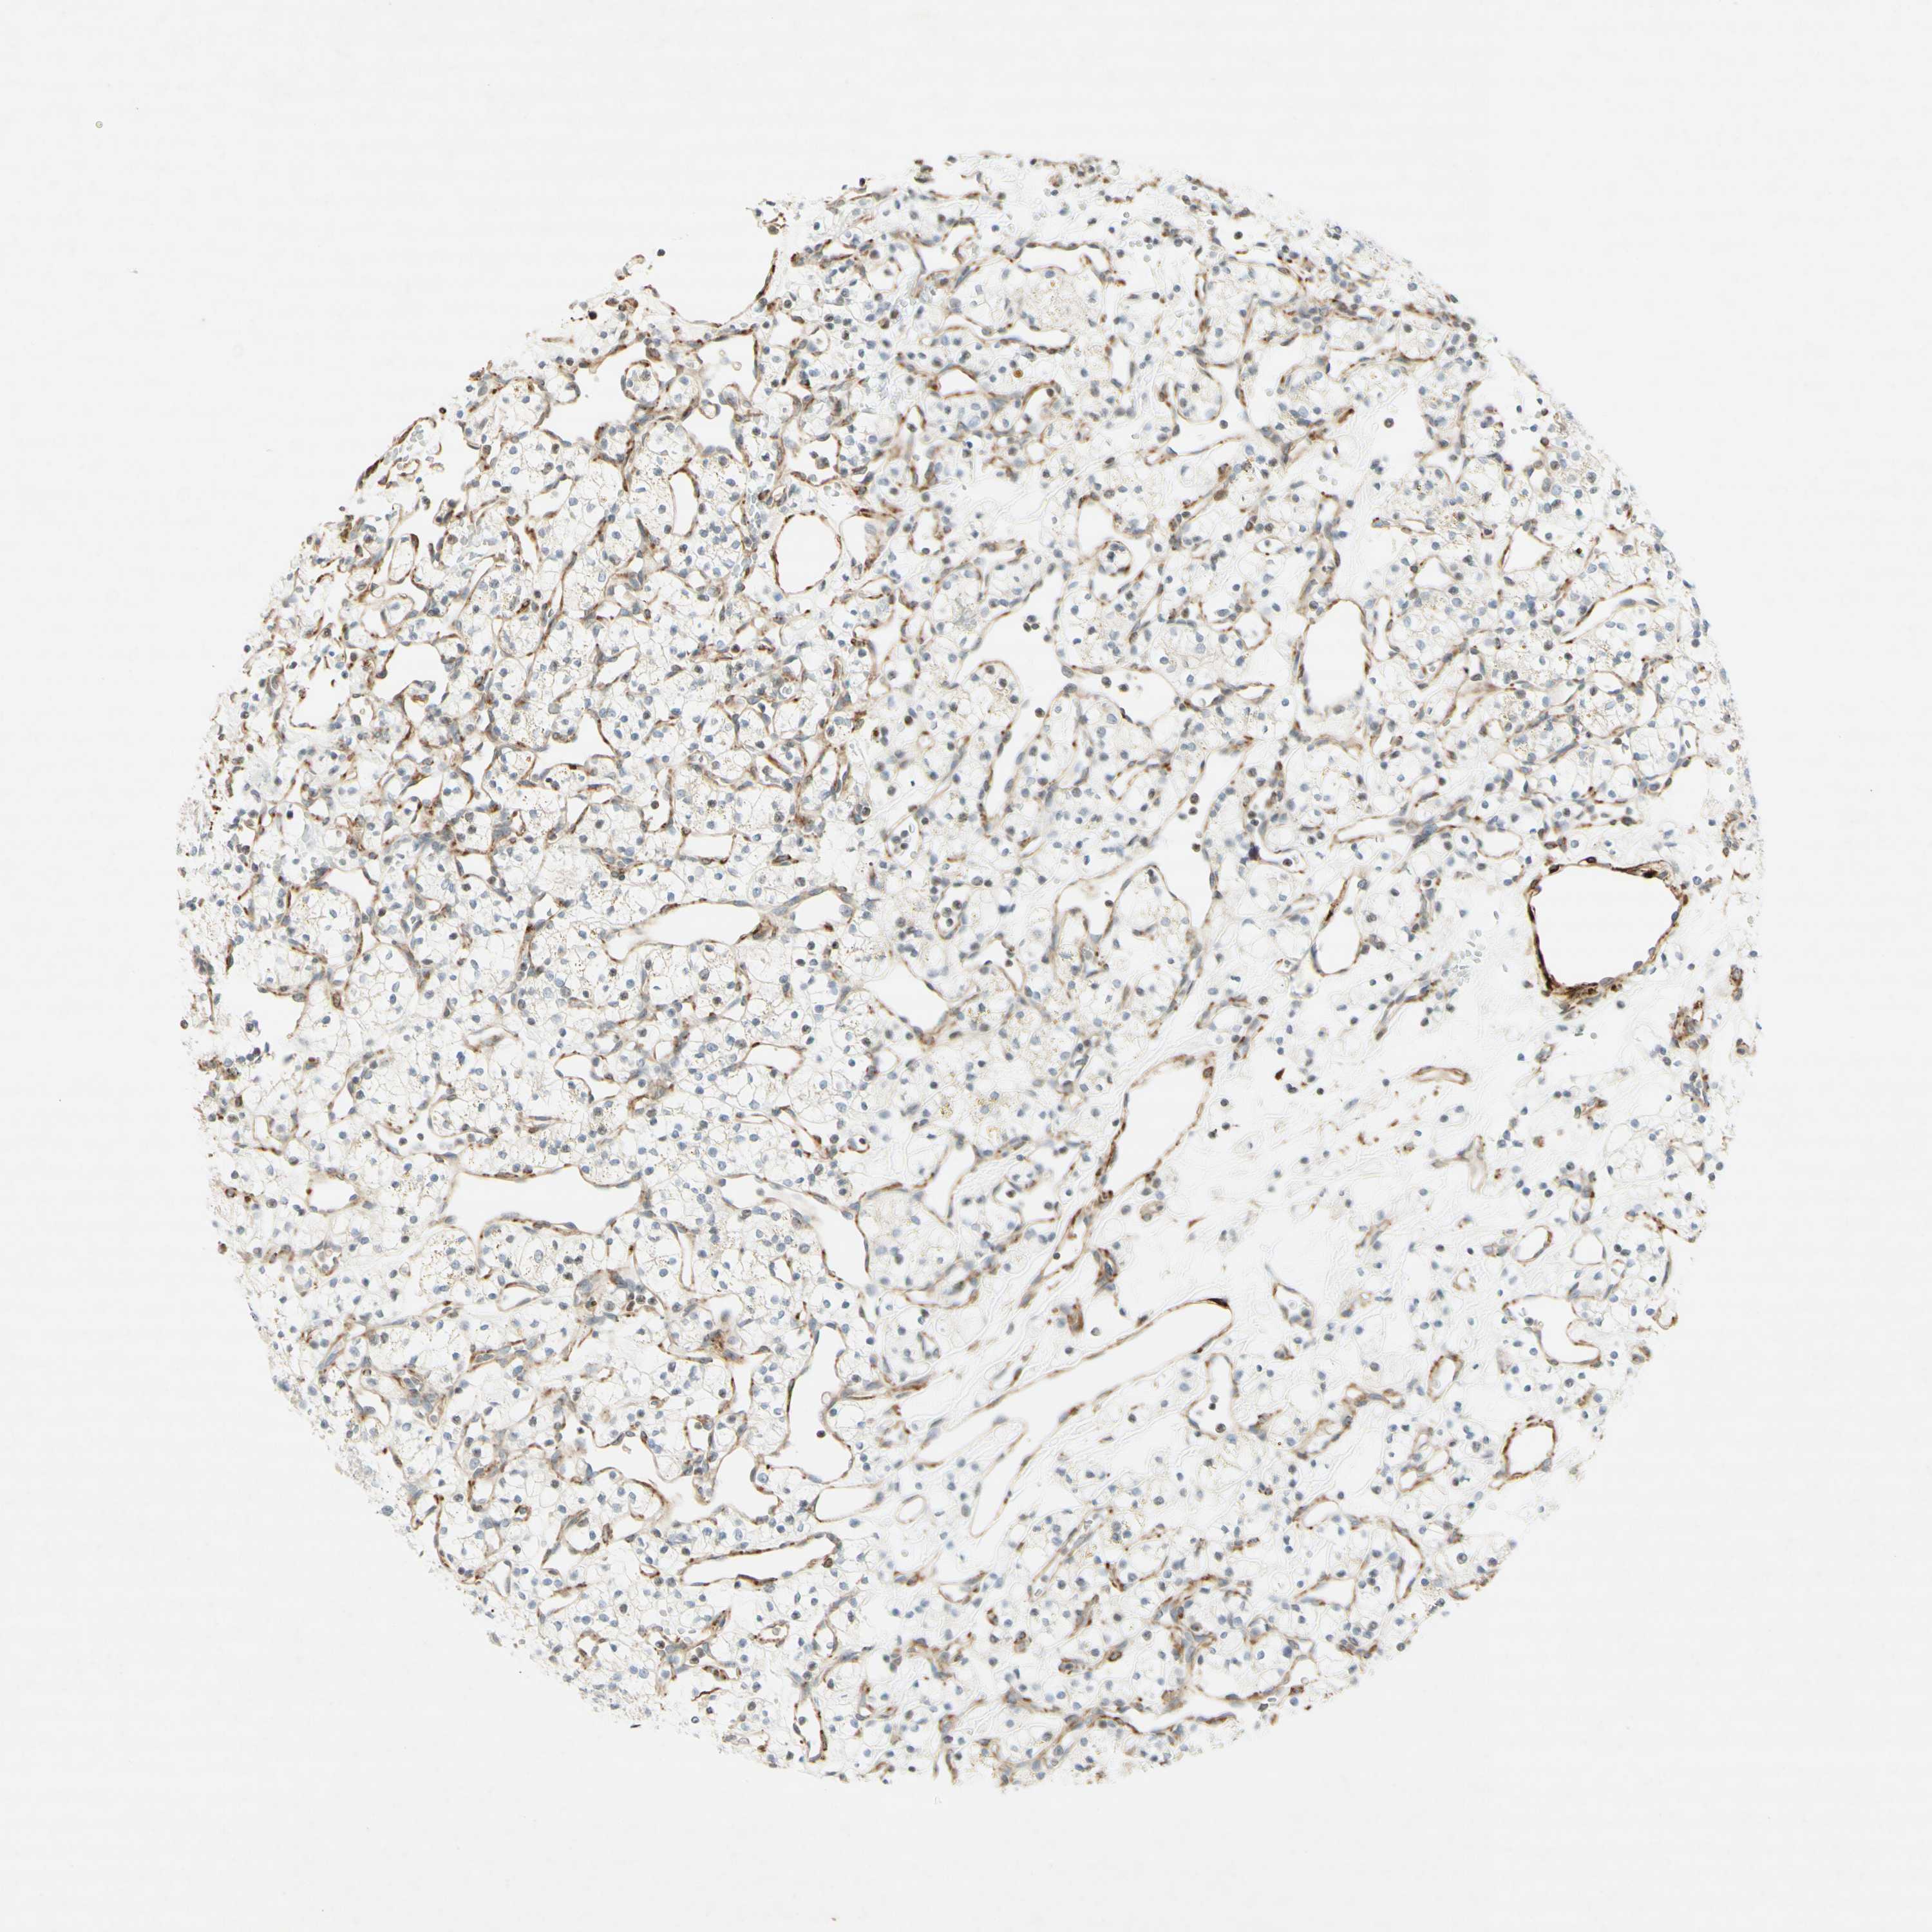

CANCER RENAL CANCER Show tissue menu

KICH TCGA KIRC TCGA KIRC VALIDATION KIRP TCGA PROTEIN RCC CPTAC PROTEIN EXPRESSION